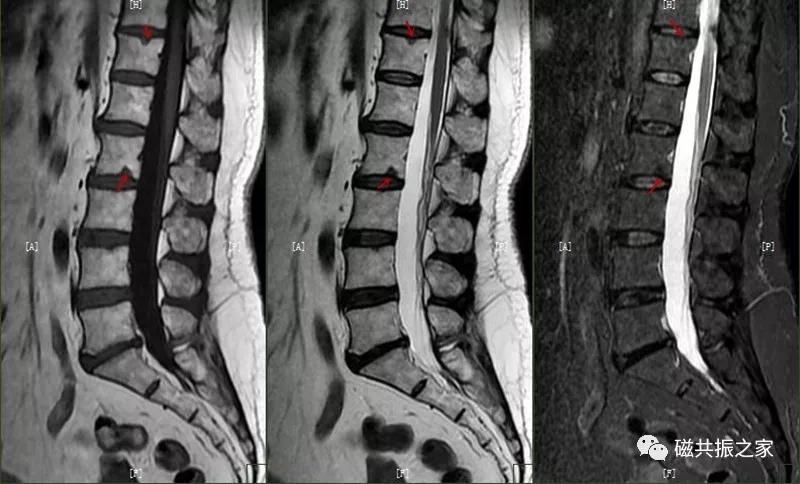

8.椎体骨折

椎体压缩性骨折常成前窄后宽的楔形改变,新鲜骨折(红箭头)常在T1WI呈低信号(出血时可呈高信号),T2WI呈低、中信号,在脂肪抑制的T2WI上呈高信号。椎体陈旧性骨折(白箭头)信号类似于正常椎体信号。如需了解脊柱骨折分型请查阅脊柱骨折的分型。